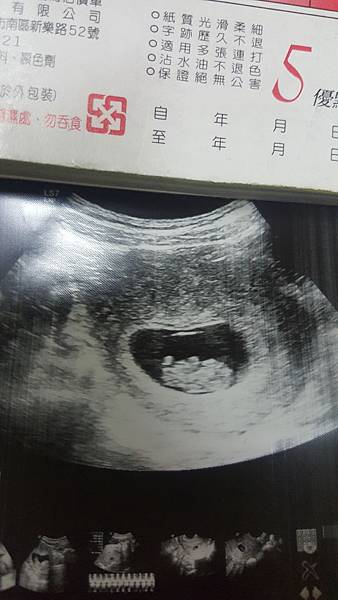

至於性別...醫生說是女寶寶哈哈哈萱萱多了一個妹妹

但是我把超音波照片貼給人家看人家卻說這男生吧因為有看到小小凸凸尖尖的東西....

還有朋友去幫我問了醫生他說只要是看不清楚的, 不確定的200%都會跟你說是女生

可是寶寶大腿真的夾緊緊大概只有30度甚至更小...不像其他的寶寶腳都超開6090度都有

昨天去產檢確定是女兒了喔陰唇照的很清楚